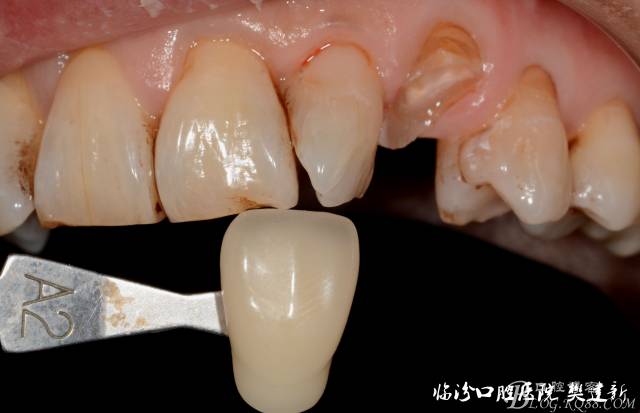

圖1  23口內(nèi)修復(fù)前情況:殘根位于齦上3MM,牙周無紅腫.

圖4 修復(fù)前選色:

640 (3).jpg